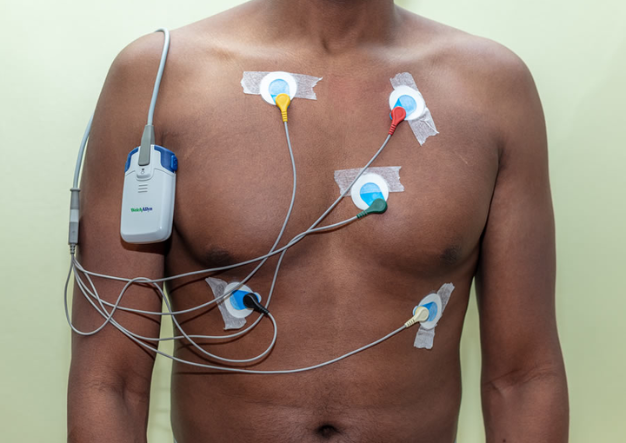

Dr. Jagannatha Raju is the best cardiologist in Vizag, offering expert heart care at Varma Hospitals.

With 20+ years of experience, he specializes in advanced diagnosis and treatment of heart conditions.